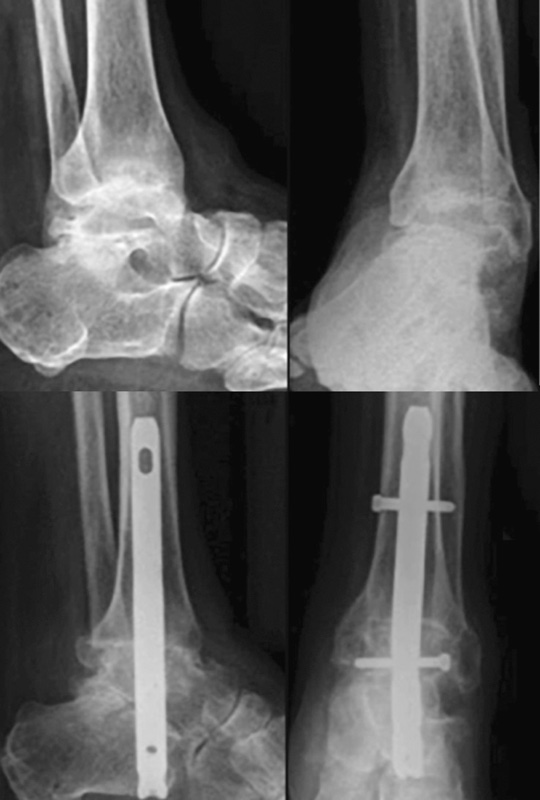

La stabilizzazione dei letti di artrodesi può essere ottenuta con il gesso (tecnica quasi totalmente abbandonata a causa dell’alto tasso di pseudoartrosi, da considerare utile come salvataggio quando non possono essere impiantati mezzi di sintesi come ad esempio nelle infezioni), mediante viti, attraverso un chiodo retrogrado tibio-talo-calcaneare (Fig. 1) o con la fissazione esterna3,4.